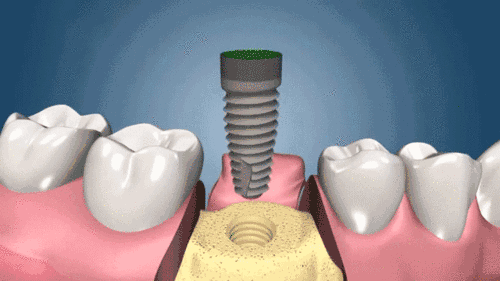

種植牙動圖

二、種植手術,醫(yī)生會根據(jù)不同顧客做出術前種植方案設計,采用手術將種植體植入牙槽骨內(nèi),種一顆種植體很快大約用10-20分鐘。

三、種植體植入3-6個月后安裝恒久牙冠,牙冠一般采用的是烤瓷材料,其外觀逼真、硬度強,非常耐用。